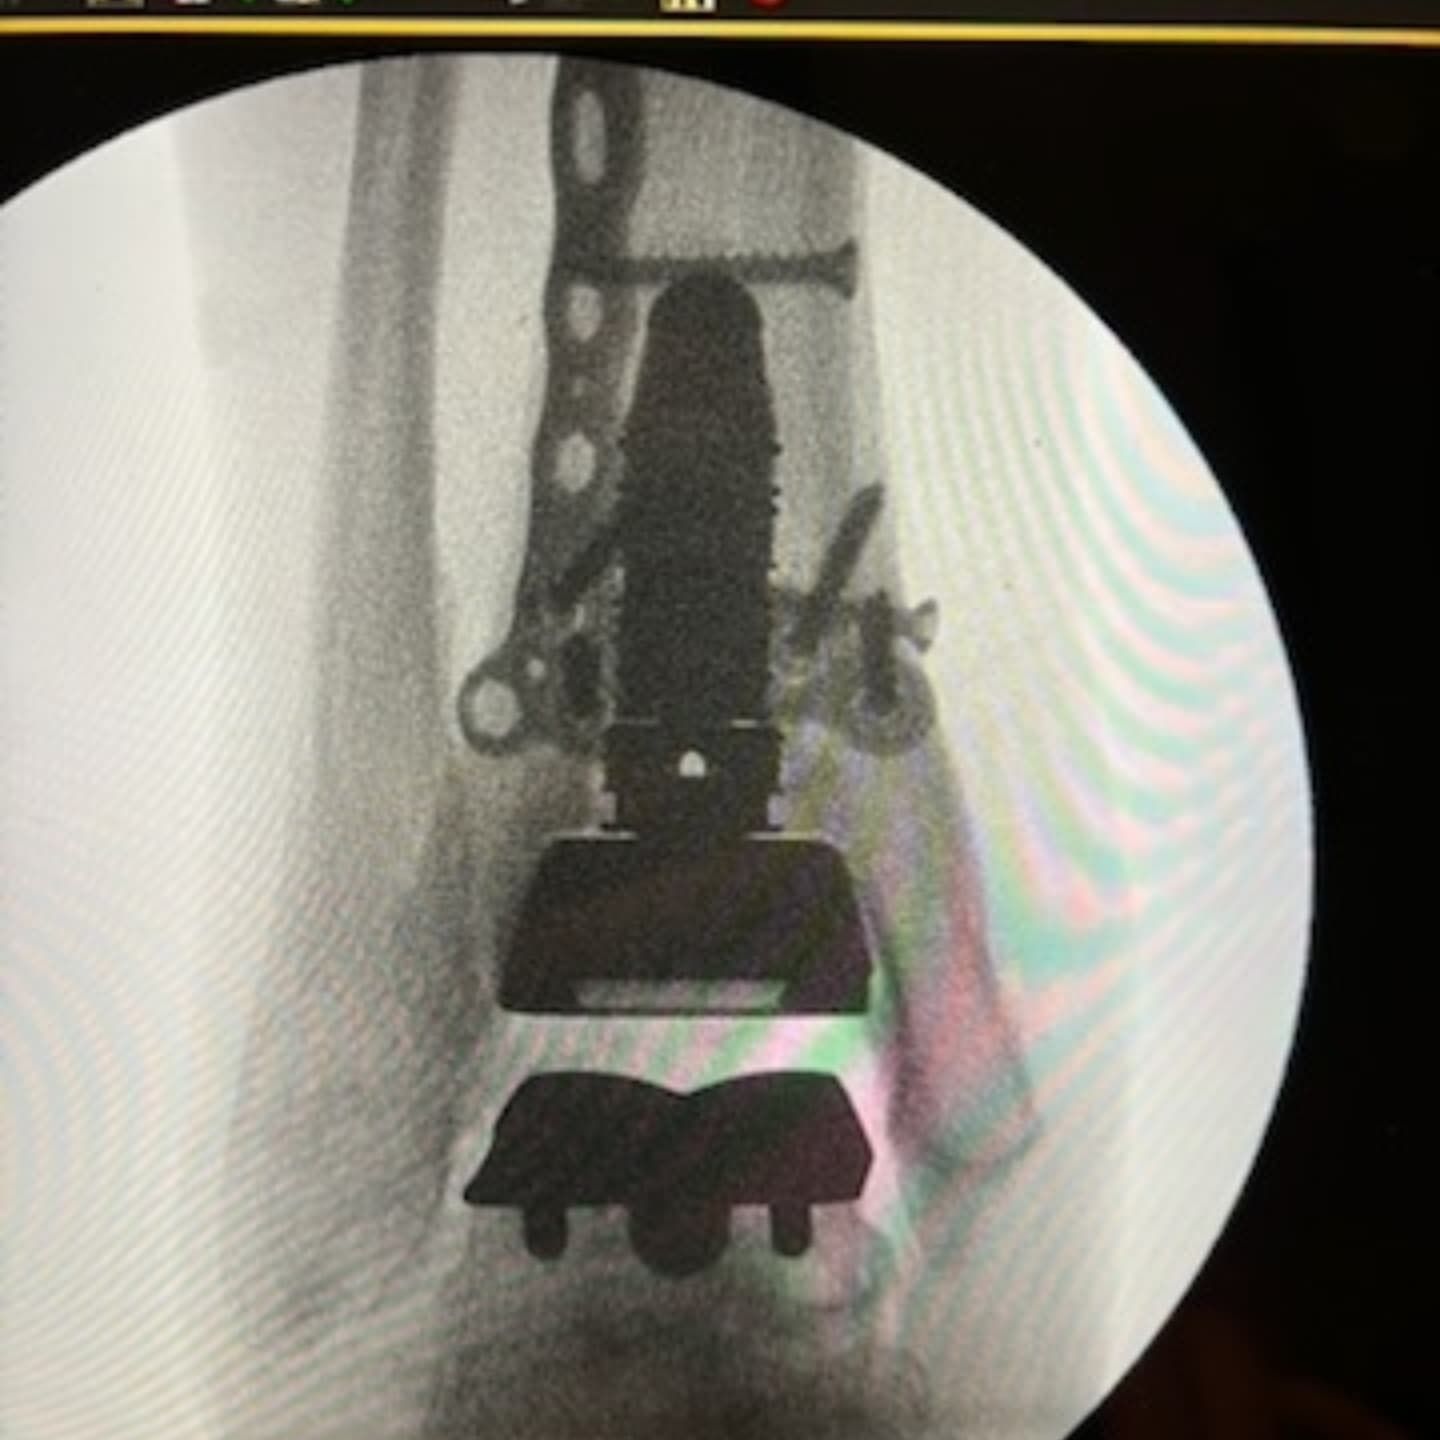

It has been a busy couple of months, but it was a pleasure to fly to Perth to help my friend and colleague Dr Unsworth-Smith with his revision ankle replacement and also to have Dr Ali Vakili observe our technique for ankle replacements.

SPECIAL GUESTS - A DAY IN THEATRE FOR MY NON-SURGICAL SUPPORT TEAM Was great to have "special guests", my own long suffering, hard working secretary @lizzie_hunter01 and podiatrist Helen from @inspire__podiatry who has helped me with my countless post op and foot and ankle patients all these years. They came to theatre to get a glimpse of how surgeries/operating theatres function, so hopefully they can understand, empathise and work better with our patients pre and post op. Helen just wanted to see a total ankle replacement 🤪.